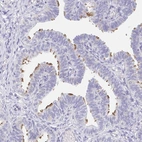

Immunohistochemistry analysis in human fallopian tube and prostate tissues using Anti-AKAP14 antibody. Corresponding AKAP14 RNA-seq data are presented for the same tissues.